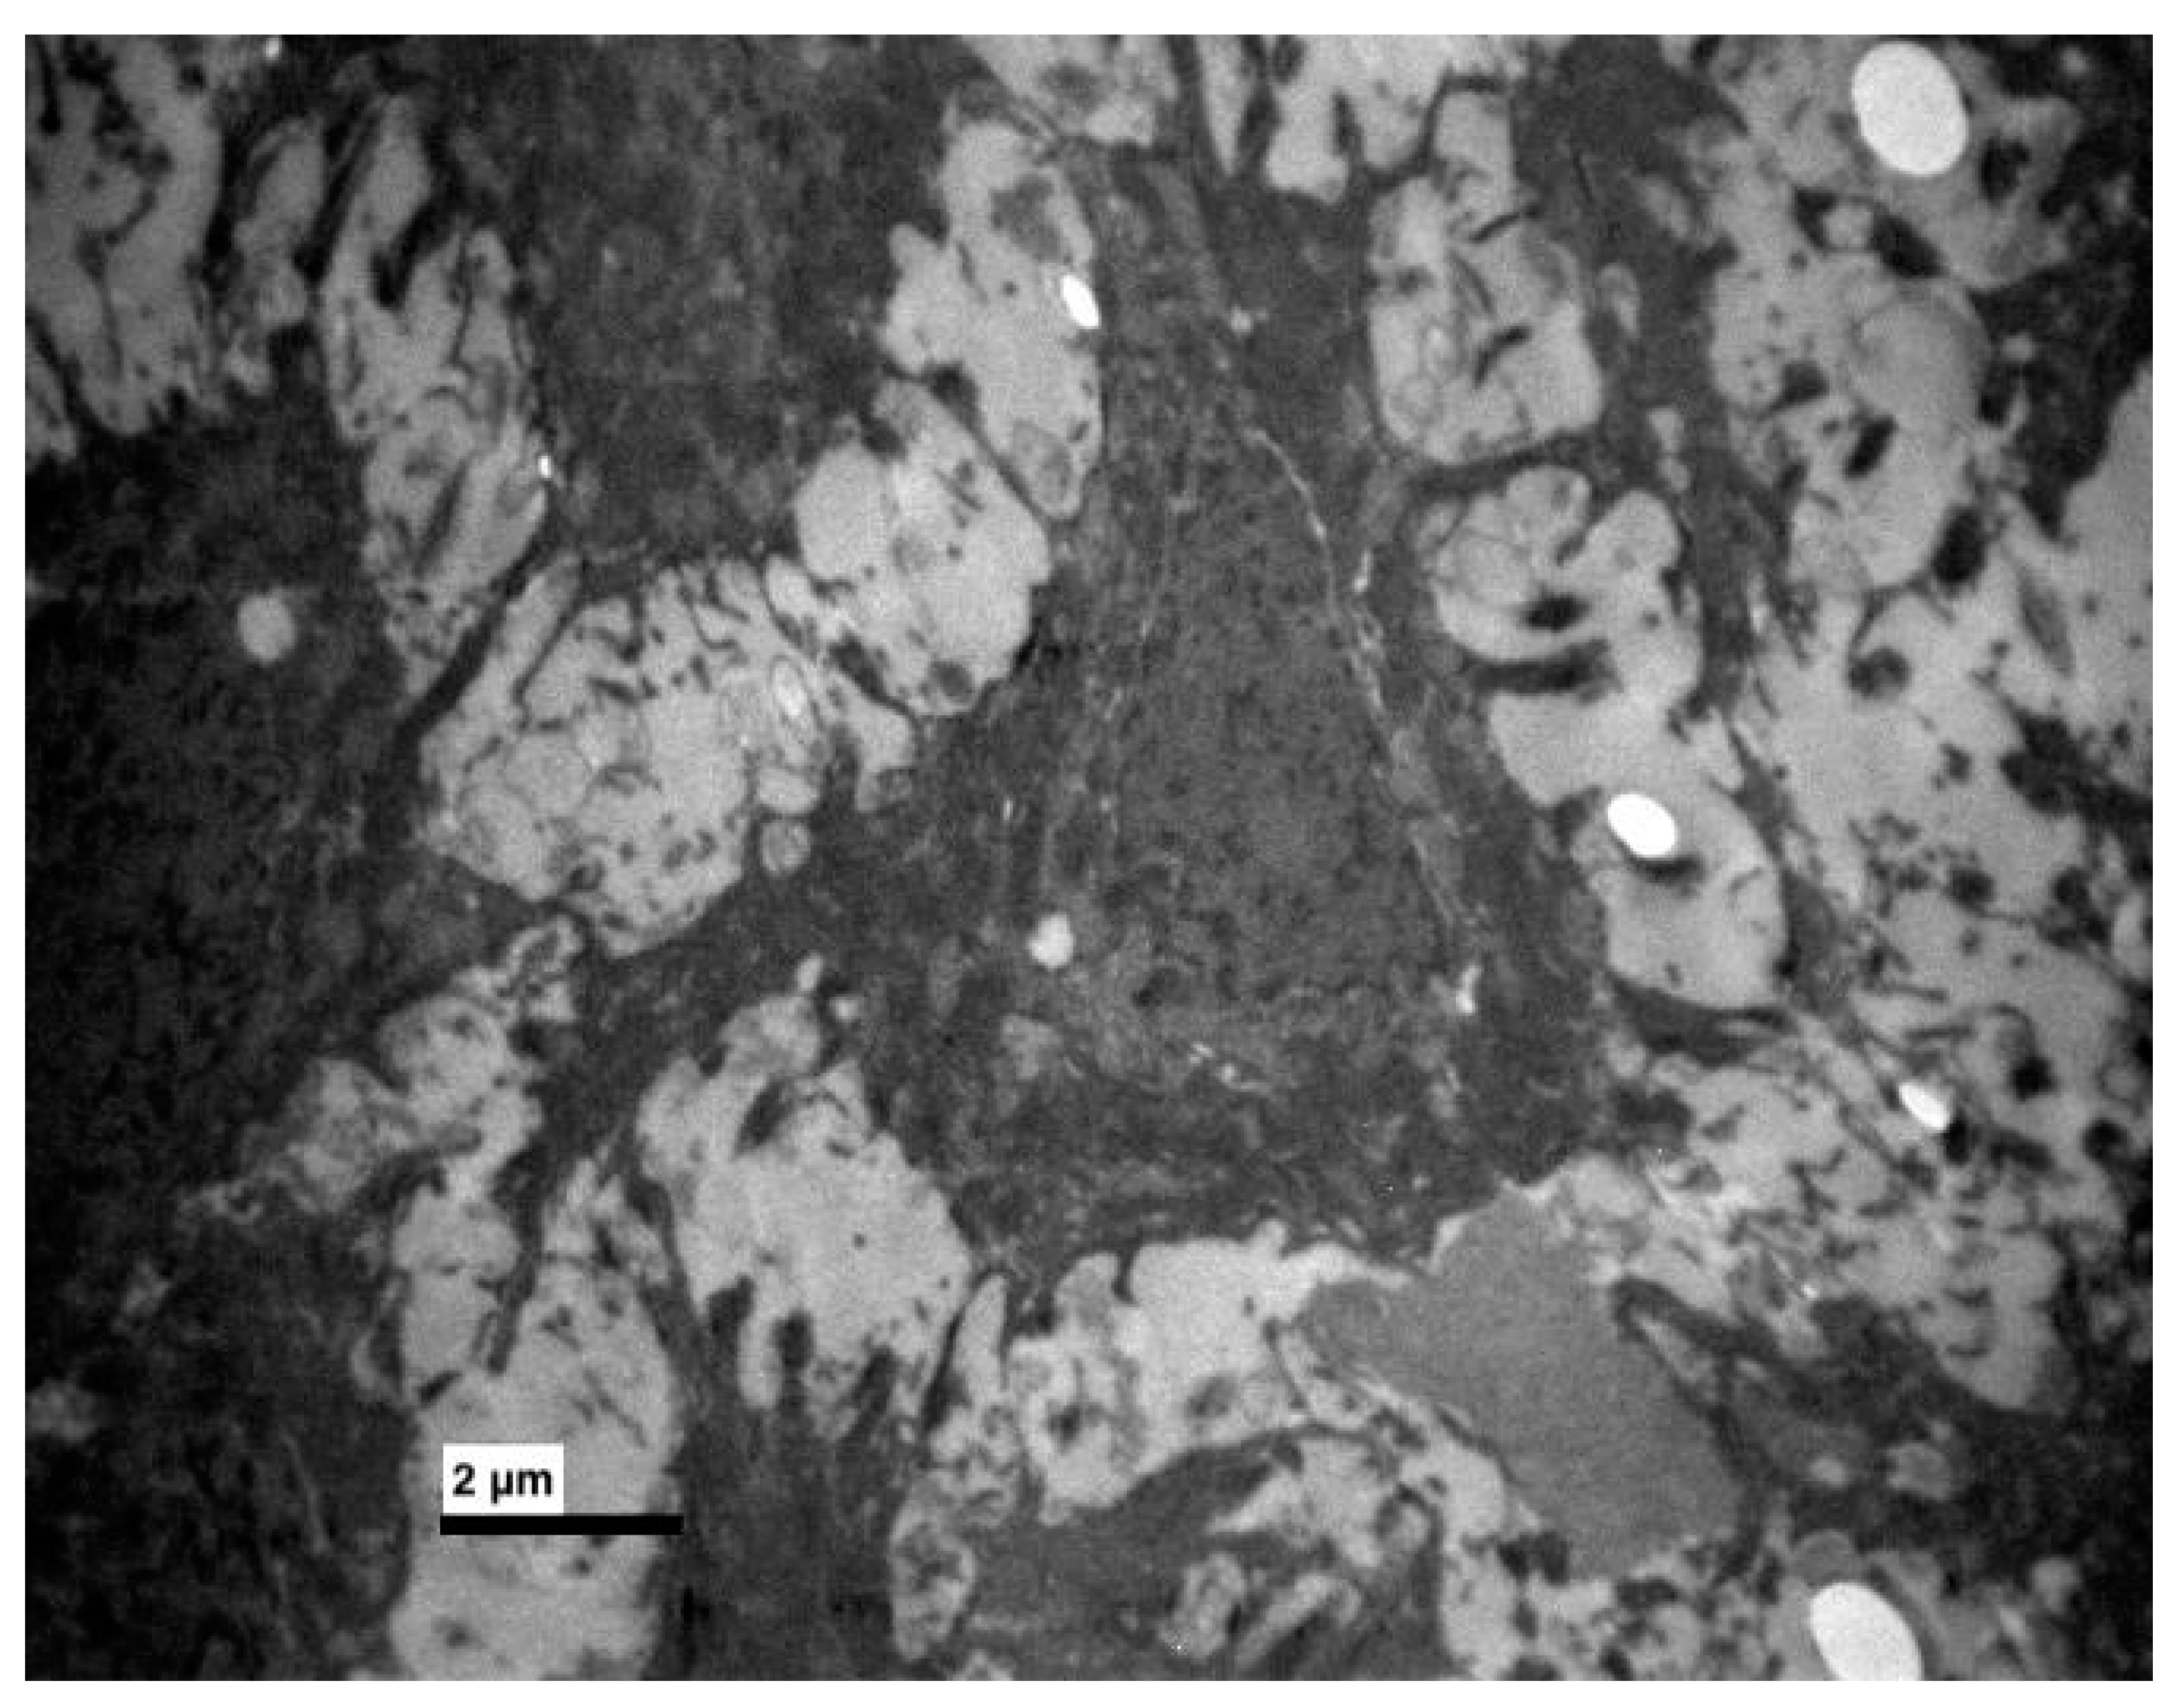

3. Results